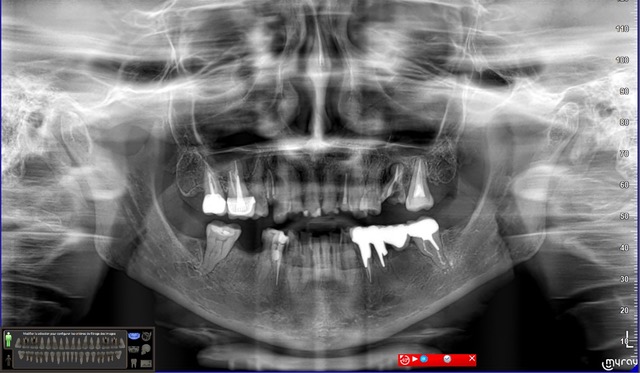

• les dents 14, 25, 26, 36 et 46 ont toutes été extraites pour des raisons de délabrements des tissus dentaires (et non pas pour des raisons parodontales),

• les dents 17 et 16 sont dévitalisées et porteuses de coiffes céramo-métalliques dont les limites vestibulaires sont exposées. La dent 36 est remplacée par un bridge céramo-métallique de 4 éléments en appui sur les dents 34, 35 et 37 (dévitalisées),

• les dents 11, 22, 27, 44, 45 et 47 présentent des obturations coronaires en composite qui présentent des signes d’infiltration,

• toutes les les autres dents présentent des signes d’érosion avancée avec des plages d’exposition dentinaires, larges par endroit, vestibulaires, linguales et/ou occlusales.

On ne note pas de signes – ni cliniques, ni radiologiques – de maladie parodontale (pas de poches, pas de mobilités…).